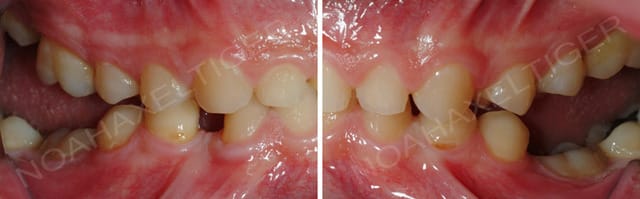

Tiens, voilà ton opposé. Celui ci a été traité par chir orthognathique.

Pre chir xidnrt - Eugenol

dans ce cas ci c'est effectivement plus difficile.!

as tu un cas de patient traité qui soit similaire au mien?